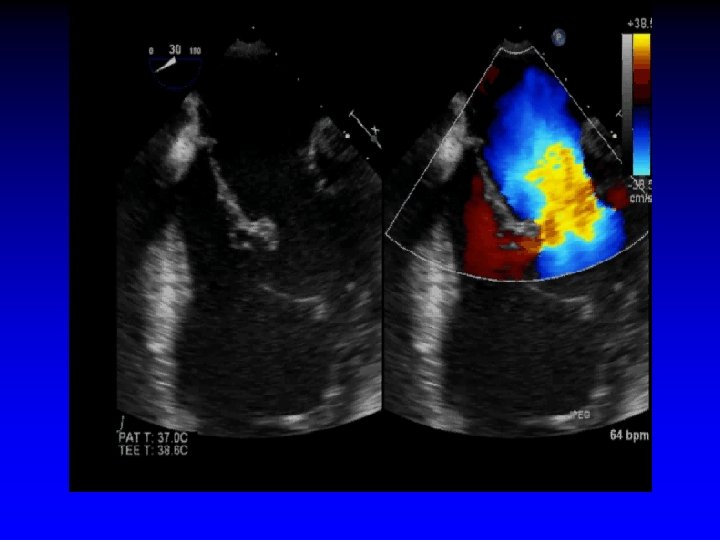

Case 1 Ruptured cords P 2

L-upper pulm vein Systolic flow reversal severe MR